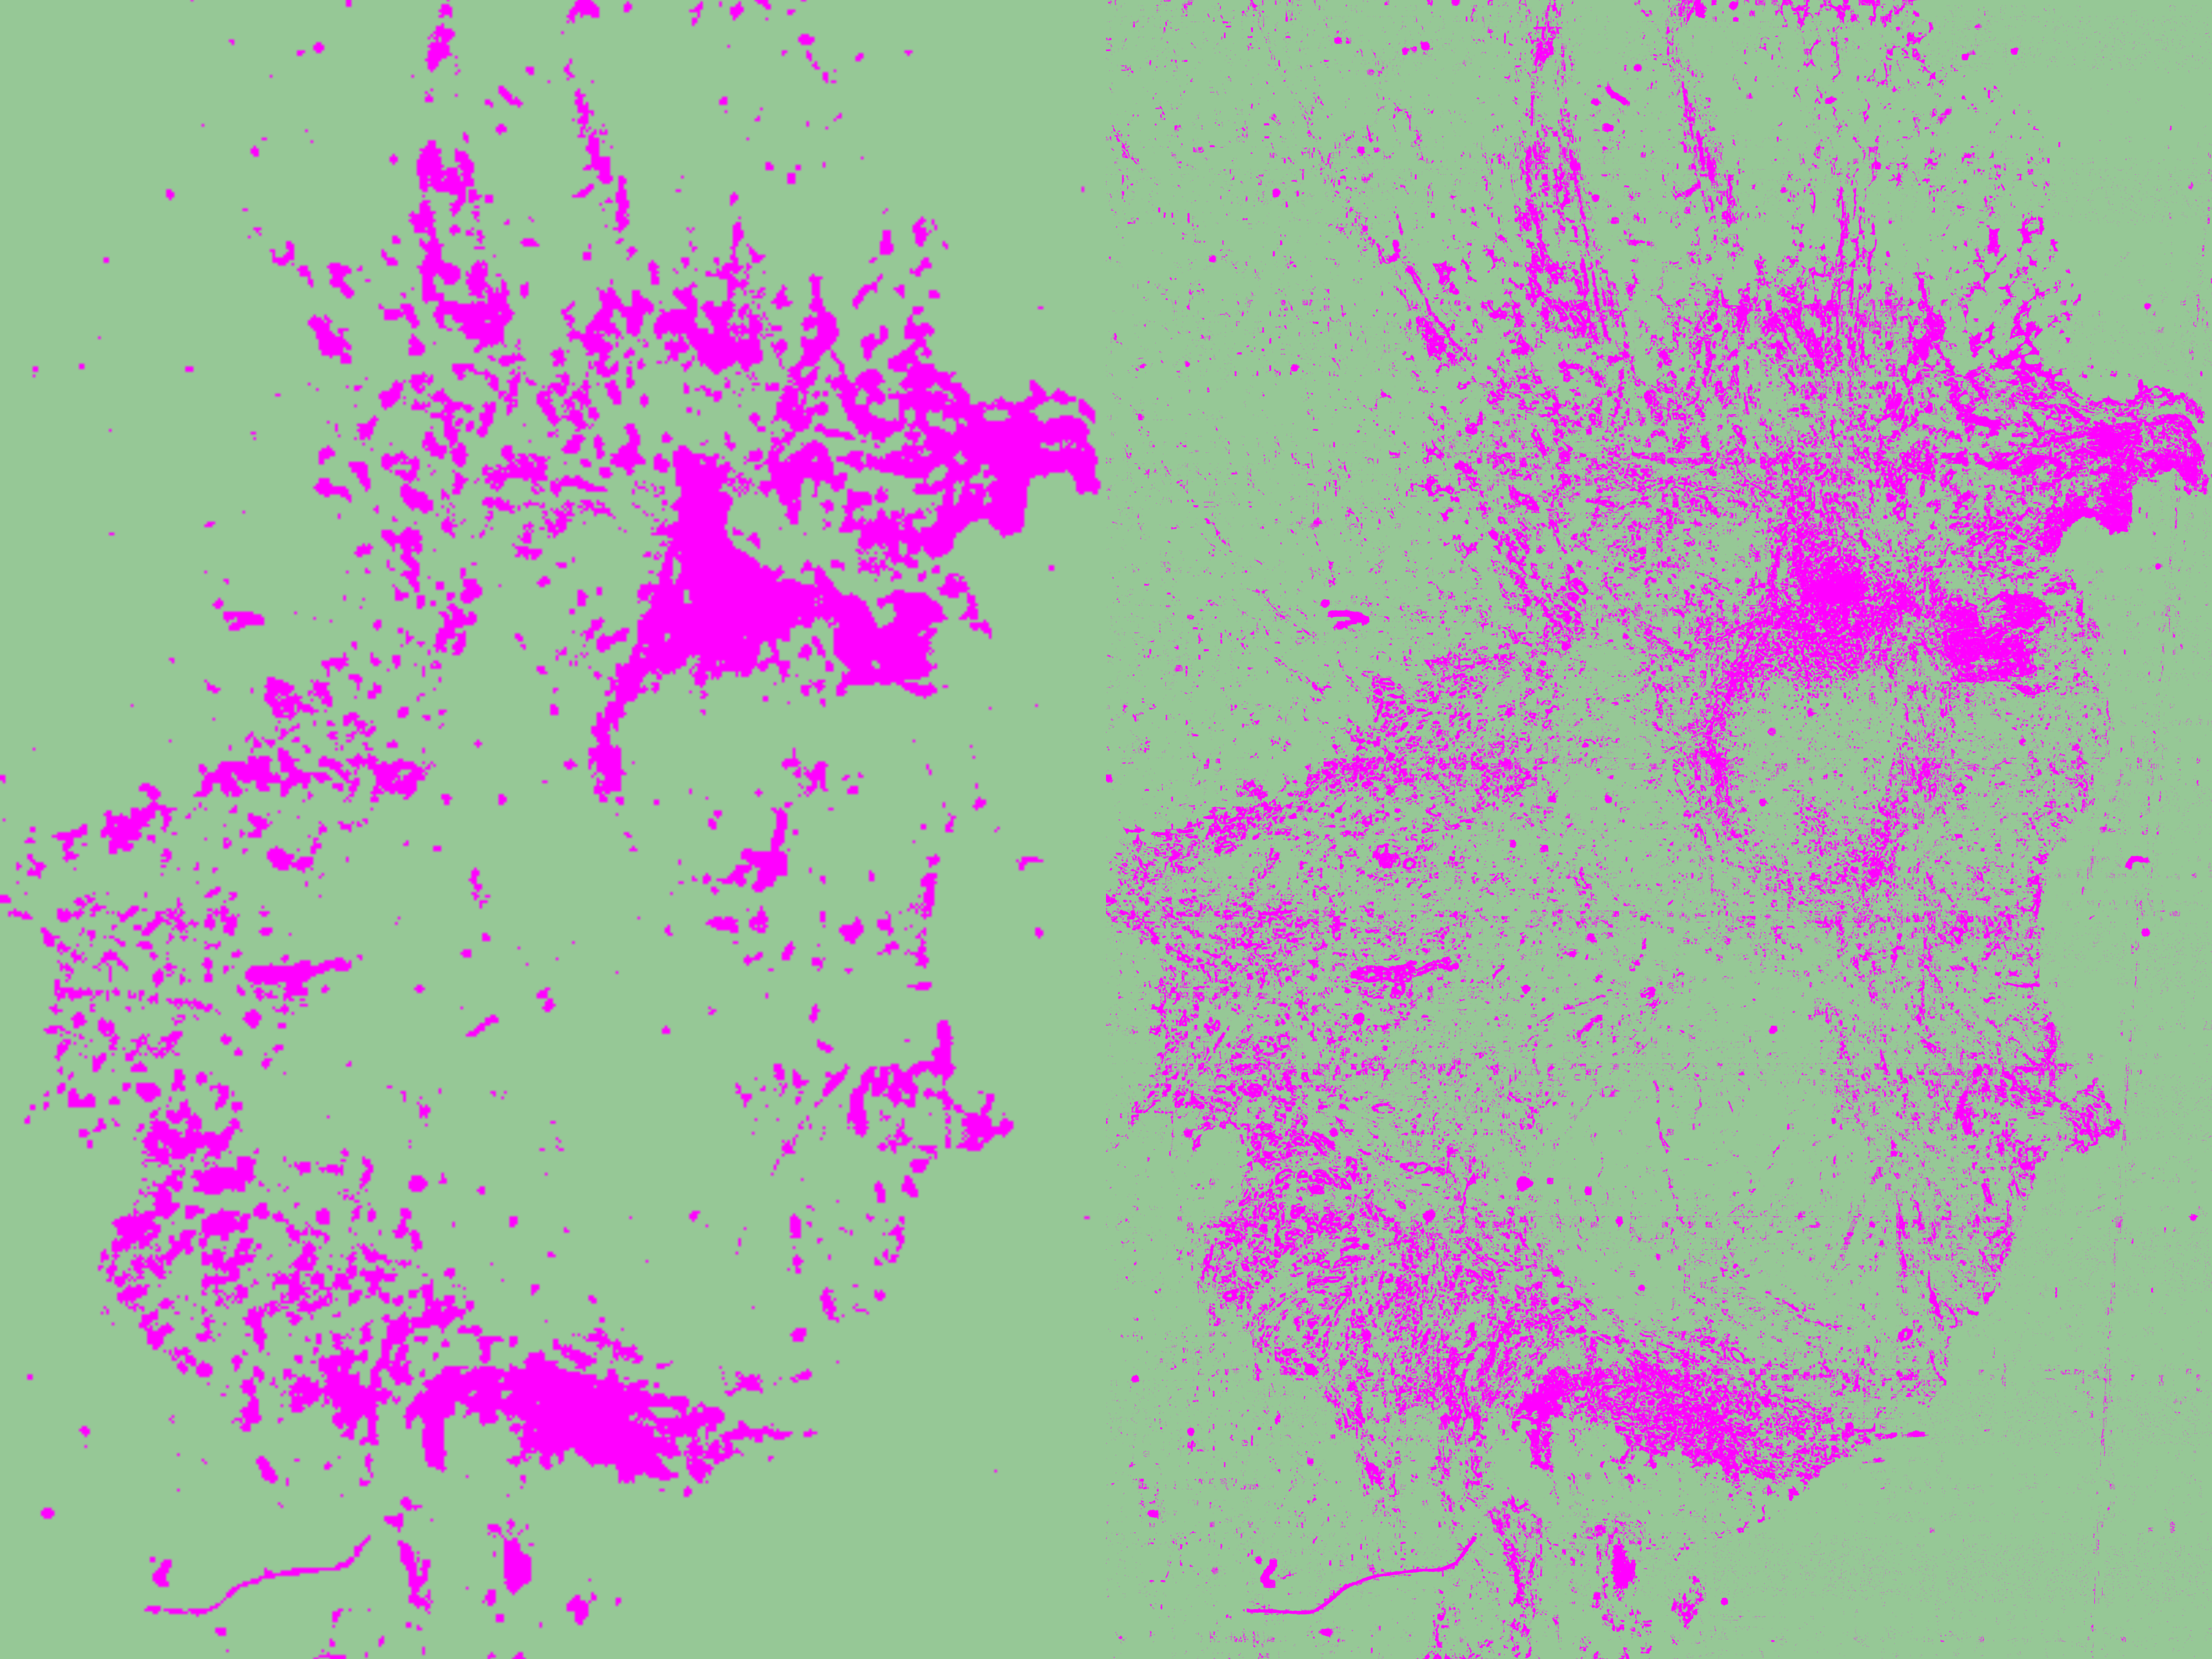

- Live Predicition: Click "Live Prediction" to preview how the classifier distinguishes between tumor and stroma regions based on your training annotations. The preview automatically updates as you modify or add training annotations.

- Review Results: If the classifier doesn’t perform well enough yet, refine it by adding, modifying, or deleting annotations. Keep the configuration panel open to observe the results as you fine-tune the training annotations. For better visibility, you can show/hide the pixel overlay by clicking the C symbol in the toolbar.

As shown in my results, QuPath detected 19.89 % tumor/epithelial area and 80.10 % stromal area in my tissue.